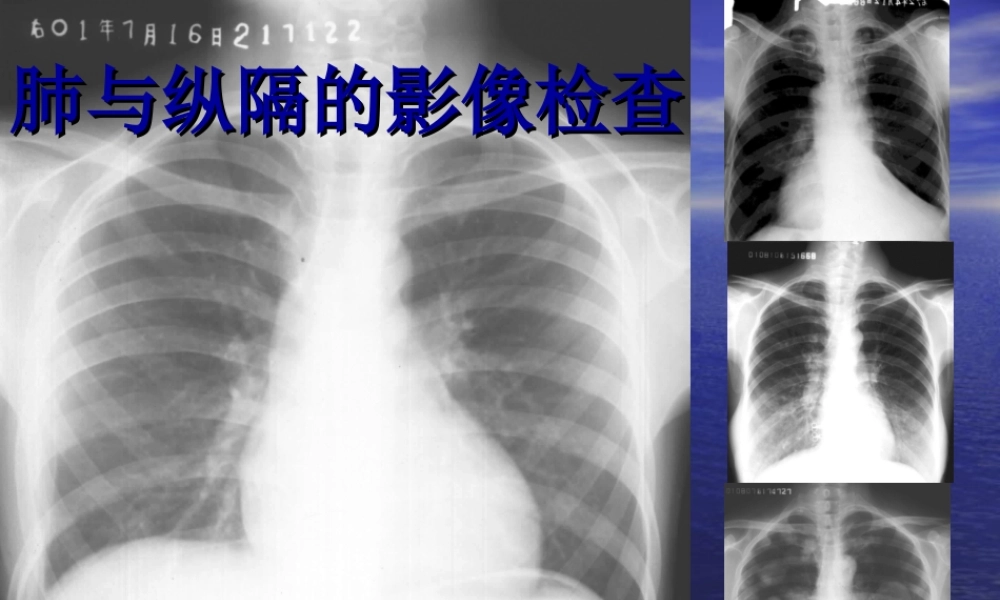

肺与纵隔的影像检查肺与纵隔的影像检查1.1.了解它的影像学检查方法。了解它的影像学检查方法。2.2.能对各个检查方法作出准能对各个检查方法作出准确的影像学诊断。确的影像学诊断。3.3.对于肺能做出它的分叶与对于肺能做出它的分叶与分段分段..并能结合并能结合CTCT做出真确判断。做出真确判断。4.4.能对常见的病例做出诊断。能对常见的病例做出诊断。肺与纵隔的检查技术肺与纵隔的检查技术•XX线检查:透视、拍片、体层、造影等线检查:透视、拍片、体层、造影等•CTCT:平扫、增强、螺旋:平扫、增强、螺旋•MRI:T1MRI:T1、、T2T2•超声成像:仅用于纵隔、心脏、胸膜疾病超声成像:仅用于纵隔、心脏、胸膜疾病胸部的正常胸部的正常XX线表现线表现•是胸腔内外各种组织结构的综合投影是胸腔内外各种组织结构的综合投影廓骨骼廓骨骼•肋骨肋骨•胸骨胸骨•锁骨锁骨•肩胛骨肩胛骨•胸椎胸椎肋骨和肋间隙常作为肋骨和肋间隙常作为胸部病变定胸部病变定位的标志位的标志•第第66前肋相当于前肋相当于9-109-10后后肋肋•肋软骨钙化顺序肋软骨钙化顺序11,,10-10-22•肋软骨钙化形式多样肋软骨钙化形式多样•变异:叉状肋、颈肋、肋变异:叉状肋、颈肋、肋骨融合骨融合胸膜胸膜•脏层与壁层胸膜间为潜在的胸膜腔脏层与壁层胸膜间为潜在的胸膜腔•斜裂胸膜:斜裂胸膜:第第4-54-5胸椎——前肋隔角后数胸椎——前肋隔角后数cmcm•水平裂:肺门向外下平第水平裂:肺门向外下平第66后肋后肋肺野示意图肺野示意图肺门肺门•正常肺门主要由肺正常肺门主要由肺动脉、肺静脉、支动脉、肺静脉、支气管等结构组成气管等结构组成•位于两肺中野内带位于两肺中野内带第第2-42-4前肋间前肋间•左侧比右侧高左侧比右侧高1-21-2cmcm肺门结构—肺门结构—22•右上肺静脉分支与右右上肺静脉分支与右下肺动脉干相交处为下肺动脉干相交处为肺门角肺门角•右下肺动脉干直径小右下肺动脉干直径小于于15mm15mm(小儿与气(小儿与气管直径相当)管直径相当)•左上肺静脉与左下肺左上肺静脉与左下肺动脉相交处为动脉相交处为肺门点肺门点肺纹理肺纹理•肺纹理主要由肺纹理主要由肺动脉分支形肺动脉分支形成成•观察肺纹理的变化观察肺纹理的变化主要依据印象、划主要依据印象、划线和对比等方法线和对比等方法肺叶肺段肺叶肺段•是肺脏的解剖结构是肺脏的解剖结构,,影像检查时只能大影像检查时只能大致判断其空间位置致判断其空间位置,,胸廓疾病时判断位胸廓疾病时判断位置有...